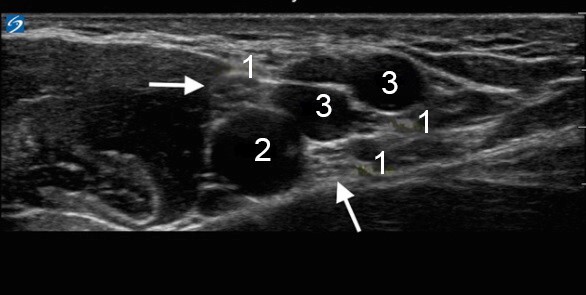

腋血管图像

神经

动脉

静脉